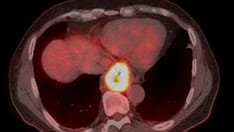

The FDA has been investigating contamination of ranitidine and a related drug with NDMA, a known human carcinogen at high doses. On April 1, 2020, the agency announced that, although its tests did not find concerning levels of NDMA in "many" of the samples it tested, it was recalling all products that contain ranitidine:

Arguably most important of all in vivo studies are those conducted in humans. One such study was completed and published in 2016 by Professor William Mitch and his team at Stanford University. 19 The study showed that healthy individuals, both male and female, that took Zantac 150 mg tablets produced roughly 400 times elevated amounts of NDMA in their urine (over 40,000 nanograms) in the proceeding 24 hours after ingestion. These results alone are extremely alarming, given NDMA has been implicated as an etiological agent for bladder cancer,20 however, the implications could be significantly worse given that NDMA is known to be heavily absorbed by the body instead of being excreted into urine.21